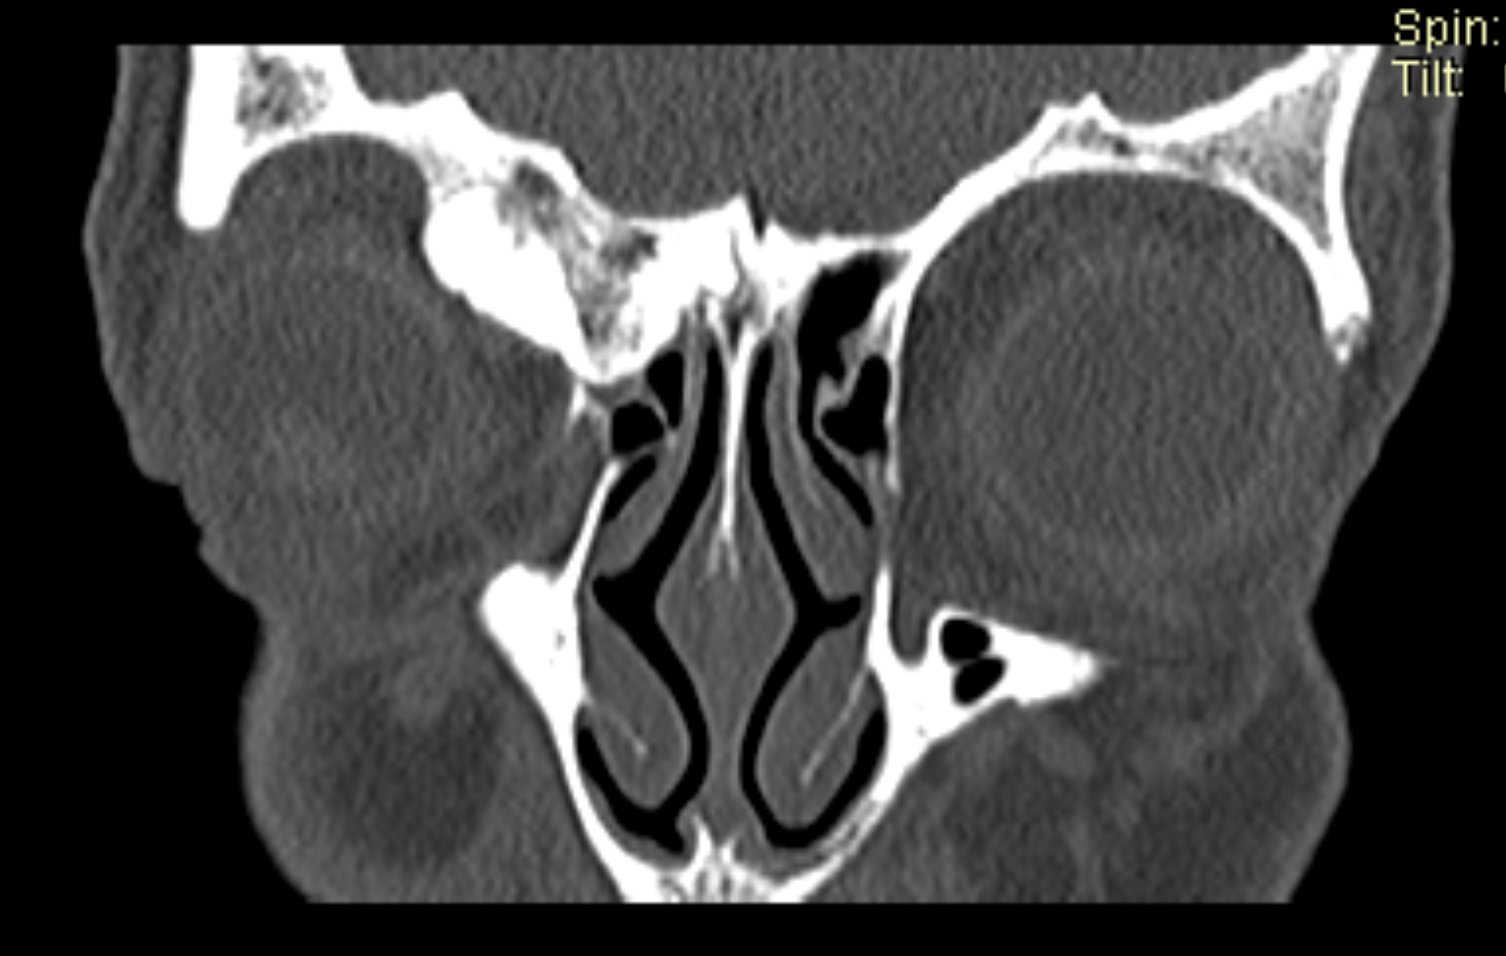

Examenul clinic ORL și examenele imagistice complementare (CT, RMN sinusuri paranazale) pun în evidență o formațiune tumorală osteogenică a sinusului frontal drept, protruzivă în unghiul supero-intern al orbitei, extinsă medial către sinusul frontal stâng.

- Se expune formațiunea tumorală osteomatoasă care ocupă în totalitate cavitatea sinusală frontală dreaptă, se extinde către sinusul frontal controlateral și către orbita dreaptă, creând presiune pe atmosfera celulo-grasoasă periorbitară la nivelul unghiului supero-intern OD. Formațiunea este intens aderentă la nivelul peretelui sinusal postero-superior. Aceasta prezintă două zone de consistență diferită.